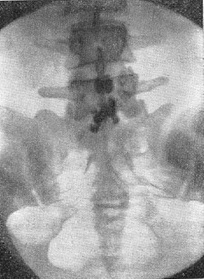

![]() Рис. 20. Розрив міжостистої зв'язки LV-SI (лигаментограмма). |

Основною скаргою хворих з пошкодженням поперекової міжостистої зв'язки є болі в області пошкодження, що посилюються при розгинанні хребта. Пальпація остистих відростків зазвичай безболісна, однак натиснення на пошкоджену межостистую зв'язку викликає різкий біль. Будь-яких неврологічних розладів зазвичай не відзначається. Для уточнення діагнозу користуються контрастною лигаментографией. Під місцевою анестезією 0,5% розчином новокаїну по 5 мл з обох сторін від міжостистої зв'язки вколюють голку строго по серединній лінії між остистими відростками на глибину, рівну половині довжини остистого відростка, і вводять при легкому тиску на поршень шприца контрастну речовину (50-70% розчин кардиотраста або диодона). В неушкоджену зв'язку входить зазвичай не більше 0,5-0,7 мл розчину, а в ушкоджену - 1,5 - 2 мл При непошкодженій міжостистої зв'язці контрастне речовина рівномірно розсовує волокна зв'язки, і на рентгенограмі видно овальна тінь з рівними краями. При розриві зв'язки і при наявності кістозних порожнин, що утворилися в результаті дегенеративного процесу, контрастне речовина дає тінь, відповідну формою і розміром порожнини (рис. 20).